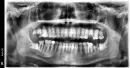

Был в стоматологической клинике, врач-хирург составил лечение и сделал снимок ОПТГ.

Хотелось бы узнать ваше мнение по этому поводу. Скажите, какие зубы исходя из этого снимка, стоит удалять, точнее необходимо, а какие нет, т.е. можно вылечить?

Под удаление идут: 1.8,2.8,3.8,4.8. Верхние не используются в акте жевания, нижние являются причиной патологических карманов. Между ними и впереди стоящими зубами имеется пространство, куда попадает пища. Возможны периодические воспаления в этих областях, неприятный запах изо рта.

Также может развиться кариес на нижних 7-ых зубах.

Что касается зубов 1.7,1.6,2.6,2.7,3.7, ревизия корневых каналов, эндодонтическое лечение, восстановление вкладками или коронками. Всё это решается с терапевтом, возможно или невозможно качественно пролечить эти зубы. Лучше сделать прицельные снимки всех этих зубов.

На зуб 4.7 необходимо сделать коронку, имеется дефект пломбы на контактной поверхности с зубом 4.6, большая часть зуба восстановлена пломбировочным материалом.

Все эти вопросы решаются на совместной консультации терапевта, ортопеда, хирурга. План лечения составляет врач стоматолог ортопед.